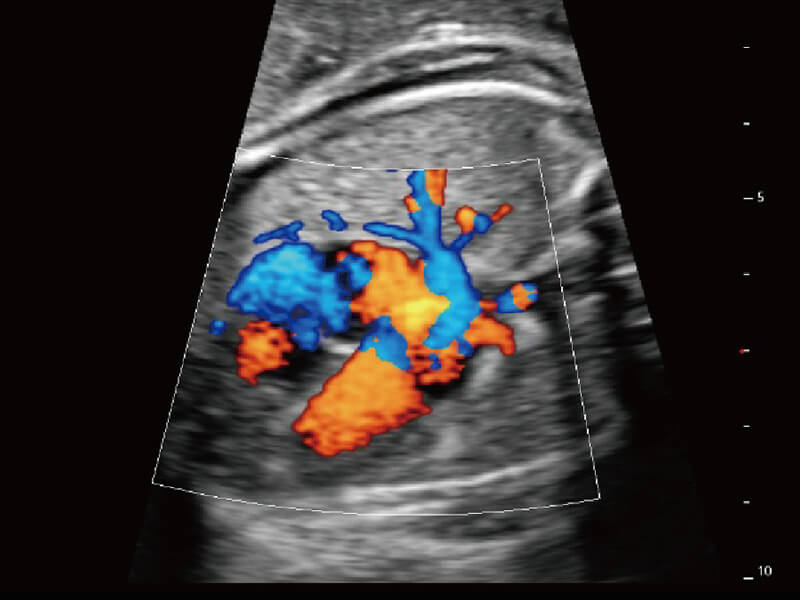

成像功能

S60探头工艺,从前端信号处理每一个环节采集无损声学数据,真实还原组织原貌,再现解剖细节。

超宽频带技术,为容积成像带来优质的二维图像基础,为您呈现丰富的结构细节,栩栩如生地展示宝宝的宫内形态以及各种组织的立体结构。